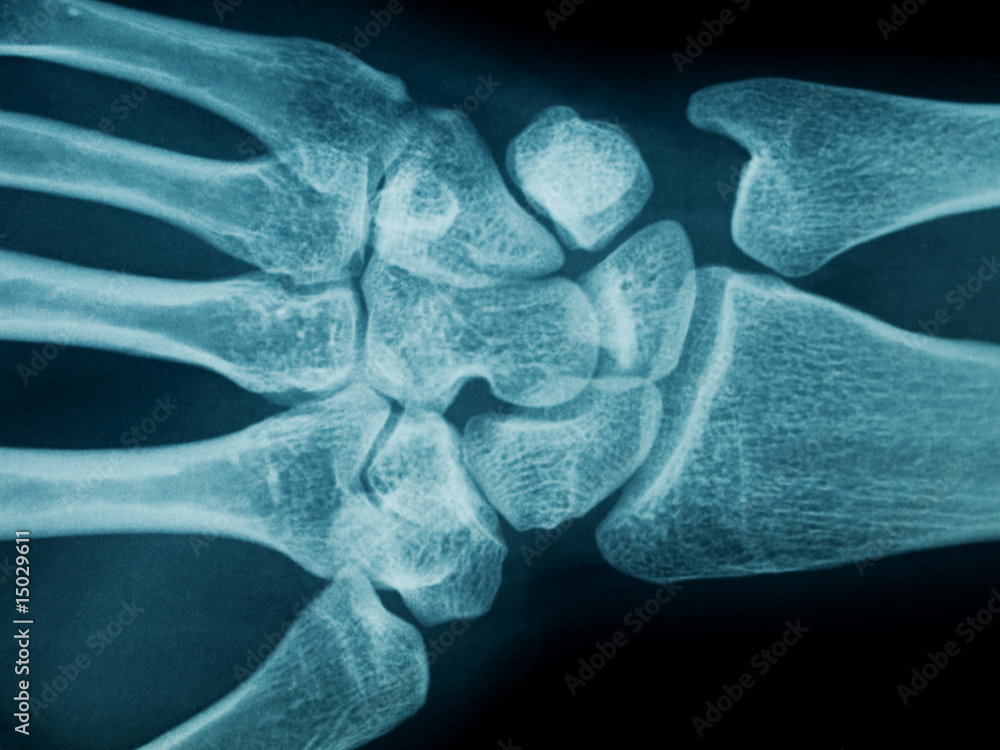

Hand wrist radiograph of a subject showing modified MP3 stage of right hand Download